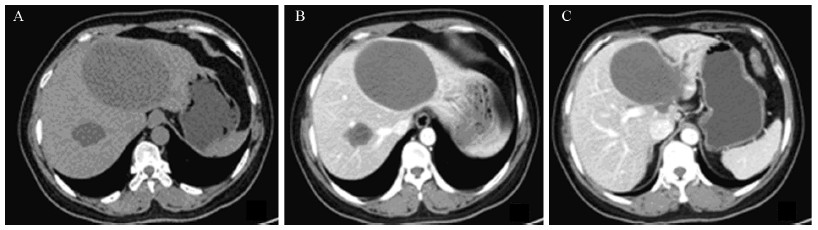

1 病例资料患者,女,45岁。因查体发现肝囊性占位1周,于2013年3月18日入住我院介入治疗科。门诊CT检查提示:肝内可见2个边界清晰、无明显强化低密度灶。较小的囊肿由于位于肝右叶且形态较小,未给予同步穿刺。较大的一个位于肝左叶,约10.6 cm×7.0 cm,压迫门静脉左支及左肝管,远端肝内胆管扩张,见图 1。入院时查体:肝左叶剑突下4 cm,质软、无压痛,余无异常。实验室检查:血清C反应蛋白5.58 mg/L、白细胞5.66 ×109/L、CA19-9 7.51 u/ml (参考值0~39 u/ml)、CA24-2 6.3 u/ml (参考值0~12 u/ml)、AFP 4.7 μg/L (参考值0~20 μg/L),入院诊断:肝囊肿;拟给予肝囊肿穿刺引流联合无水乙醇硬化微创治疗。

| A:plain CT scans showed two low-density lesions in both hepatic lobes,the left lobe's cyst was bigger and measured as 10.6 cm ×7.0 cm in diameter,with a clear demarcation;B:the contrast enhanced CT scan showed that there were uniform low-density areas inside the cyst and the cyst wall was without significant enhancement;C:the boundaries between the cyst wall and the surrounding structures was unclear,the left portal vein and left hepatic duct were pressed and the distal of intrahepatic bile duct was dilated 图 1 肝囊肿穿刺引流前CT平扫及增强表现 Figure 1 CT findings of plain scans and contrast enhanced scans before a percutaneous transhepatic drainage of hepatic cyst |